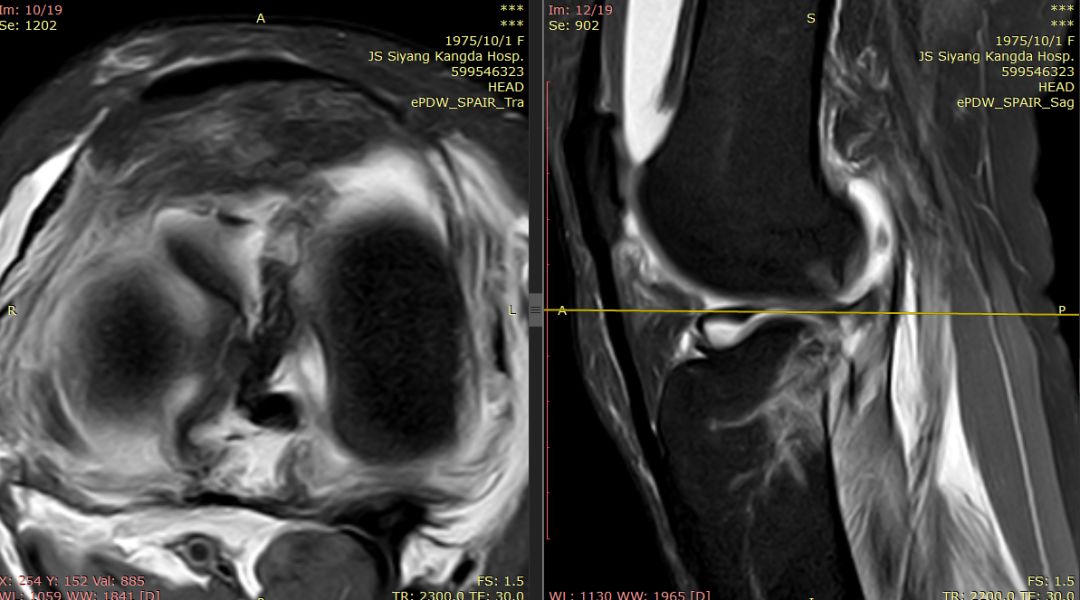

下图标记的是外侧半月板的撕裂

下图示外侧副韧带损伤 腘肌腱损伤 髂胫束连续

内侧副韧带损伤

膝后肌群损伤